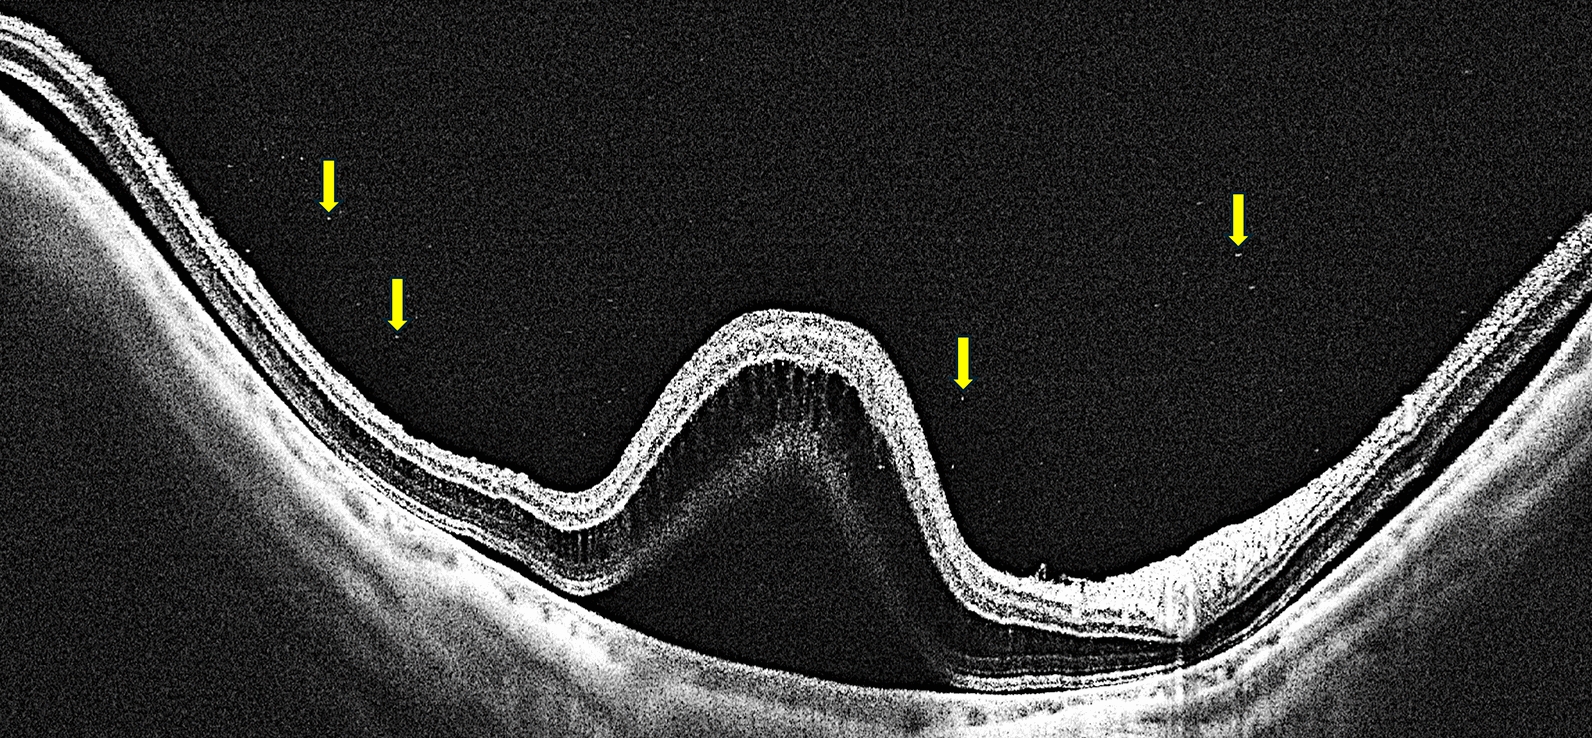

The UWF-OCT examination revealed that both the posterior pole and the mid-periphery of the retina were affected (Fig. 1). During the acute phase, we also detected SS-OCT hyperreflective foci in the vitreous chamber that were not visible on ultrasonography (Fig. 2). These foci partially persisted until 1 year after surgery. In two patients, the resolution of the macular serous retinal detachment led to visible structural OCT damage of the outer retina, which is likely to be permanent (Fig. 3). UWF-OCTA revealed an increase in SVD in the posterior pole and mid-periphery during the acute phase, while at the resolution of subretinal fluid, SVD decreased; it was only partially restored but did not return to preoperative values after 12 months. The deep vascular complex, choriocapillaris, and choroidal circulations did not appear to be damaged. Vascular involvement included not only the macular region but also the retinal mid-periphery (Fig. 4). Multifocal ERGs, after the loss observed at T1-T2, showed a gradual recovery of the foveal response amplitude at T3-T5 (Fig. 5).

Fig. 2

Ultra-wide-field optical coherence tomography during acute intracameral cefuroxime ocular toxic syndrome. Arrows indicate hyperreflective foci. Image contrast has been adjusted for vitreous visualization